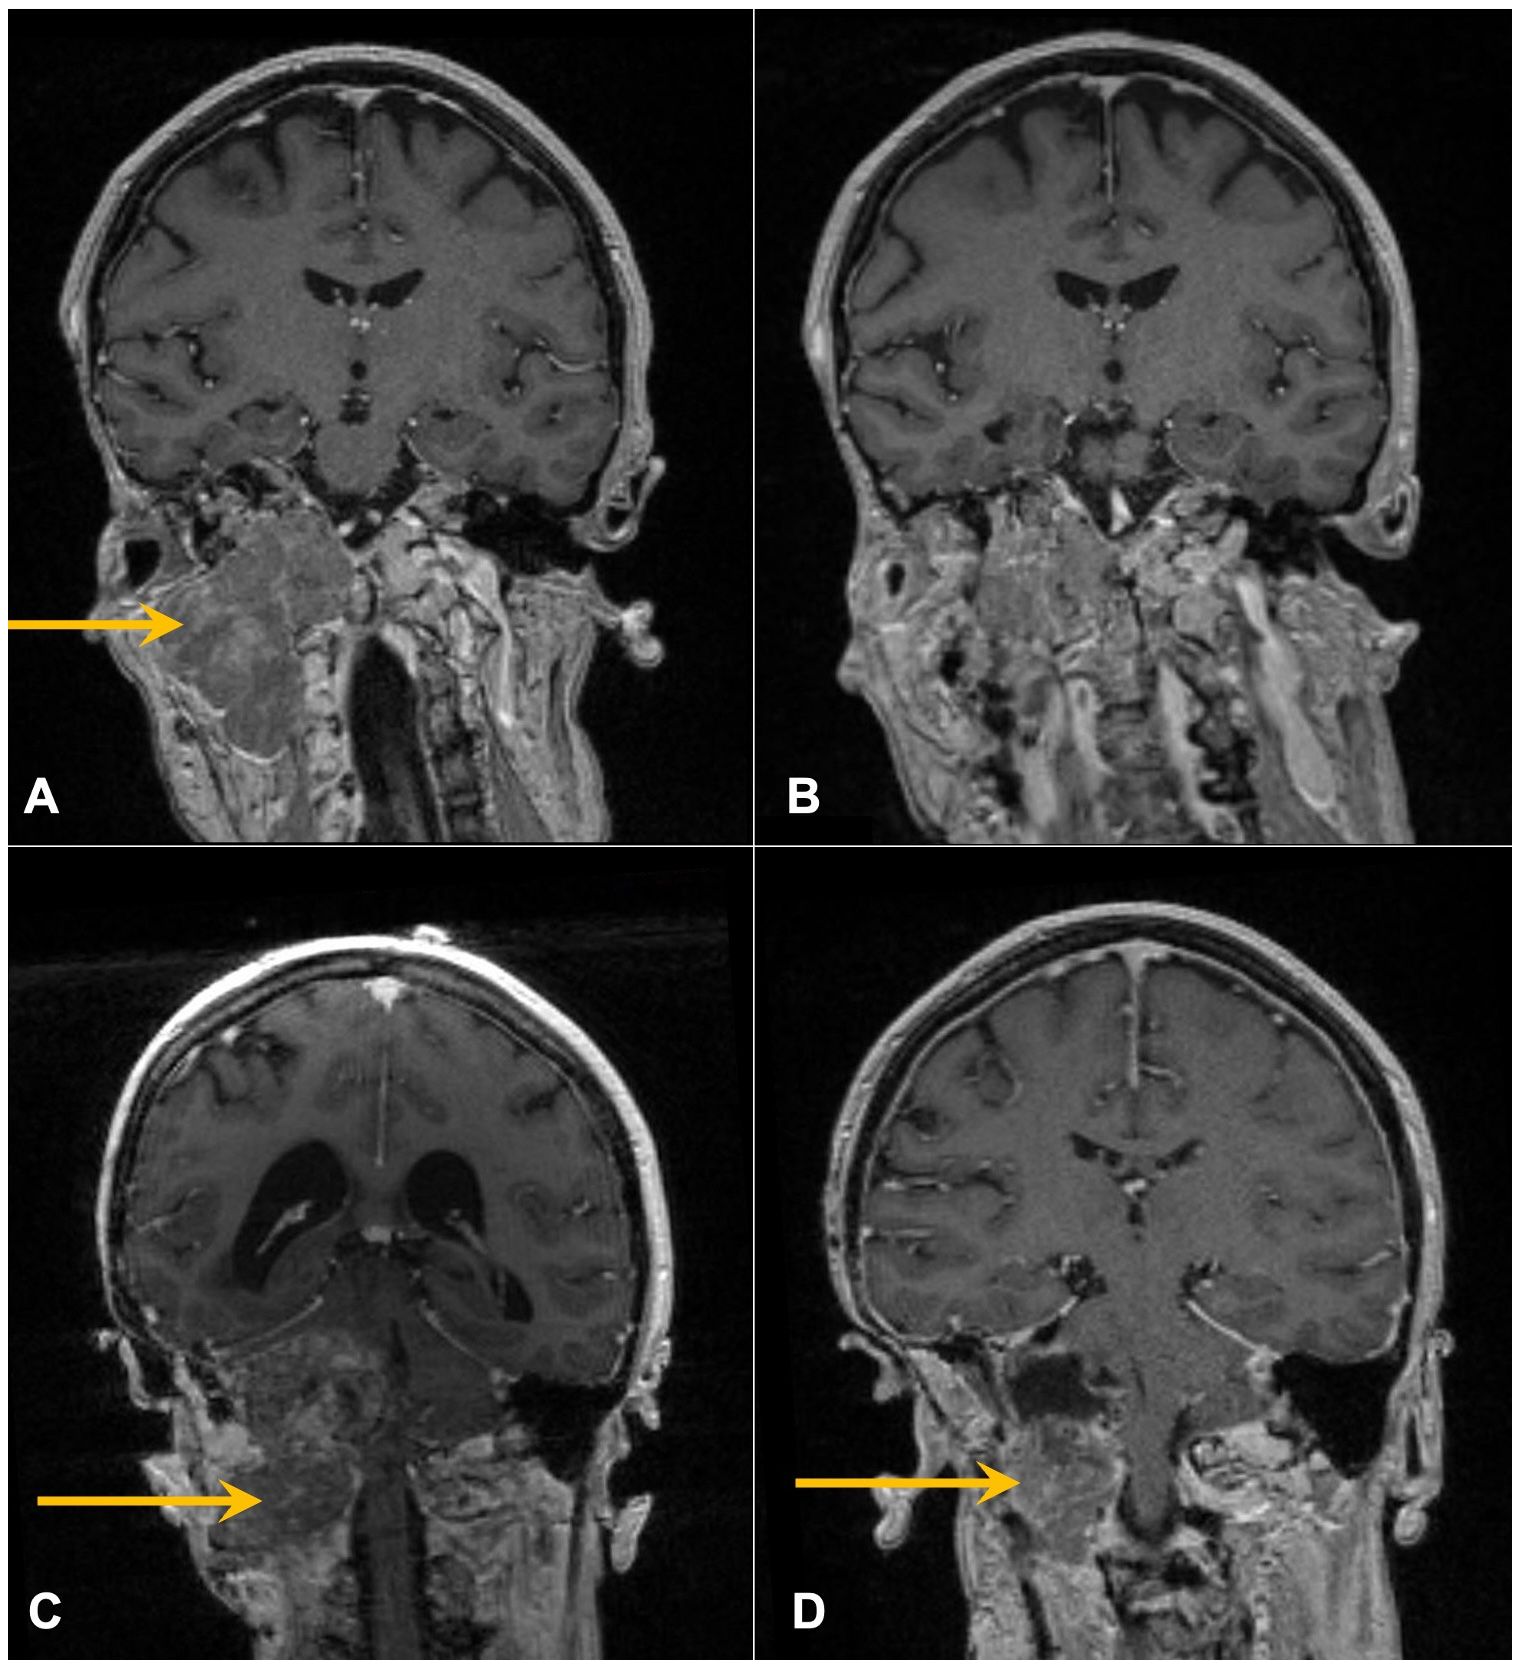

In 1993, at age 19, our patient was diagnosed with atypical meningioma, grade 2, located around the right mastoid region. Her treatment plan included two closely spaced surgeries and proton therapy, followed by surveillance for more than a decade. She lacked a family history of neurofibromatosis 2 (NF2) or cancer, as well as clinical or imaging evidence of NF2. Referral for genetic counseling was refused. In March 2017, at age 43, she developed progressive headaches, and imaging demonstrated an enhancing right upper neck mass with erosion of C1–C2 and extension into the posterior fossa (Figure 2A). Her first surgical resection (R1) following recurrence was performed in April 2017, and pathology demonstrated atypical meningioma lacking immune infiltrates. The post-surgery MRI and histopathology (H&E) images are depicted in Figures 2B, 3A, respectively.

Four MRI scans of the head are shown in a grid. Image A highlights a mass on the left side with a yellow arrow. Image B shows a similar view without the mass. Image C depicts a scan from a lower section with another mass indicated by a yellow arrow. Image D shows a mass adjacent to the sinus area, also marked with a yellow arrow.

Figure 2. Contrast-enhanced coronal T1 MRI of the brain following recent surgeries. Arrows mark enhancing skull base mass prior to R1 (A) and R2 (C) and resulting post-operative images following R1 (B) and R2 (D).

She initiated somatostatin analog injections in July 2017, which she continued monthly for 22 months until imaging in November 2018 demonstrated progression (2123). She also developed mild headaches, tearing in her right eye, and decreased movement in the right side of her face. The decision was made to undertake a large cancer-based surgery, R2 (Figures 2C, D), in April 2019. Pathology from this surgery was similar to that of the R1 specimen (Figure 3B).